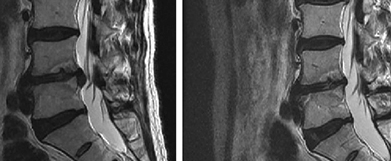

Starpskriemeļu diska trūces rezorbcijas metode

Kā notiek rezorbcija?

Samazinoties starpskriemeļu diska trūcei, pacients sāk justies atvieglojums un akūts sāpju sindroms pamazām pārvēršas nelielā diskomfortā un pēc tam pazūd pavisam. Sāpju simptomu izzušanas ātrums ir 1-3 mēneši, bet atsevišķos gadījumos tas var aizņemt ilgāku laiku, atkarībā no organisma īpatnībām un trūces veida.

Šie divi faktori ietekmē rezorbcijas kvalitāti un veiksmi. Pat ja rezorbcija notiek pati no sevis (mazāk nekā 40% iespējamība), literatūrā ir aprakstīts vidējais termiņš 12-18 mēneši, atkarībā no diska bojājuma pakāpes un organisma spējas atjaunoties.